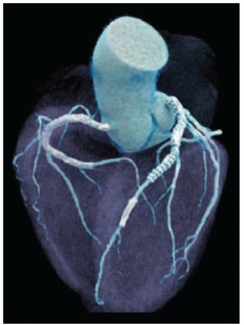

Case Report

03/01/2024

Steven Kernis, MD;  Kishore Harjai, MD;  Arthur Martella, MD

Reprinted with permission from J INVASIVE CARDIOL 2014;26(8):E117-E119.

This case report illustrates the remarkable benefits that 1 patient received over a 40-year span from milestone achievements in cardiac surgery and interventional cardiology.